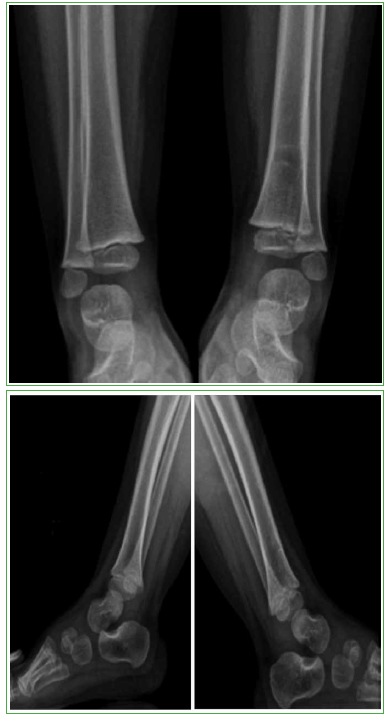

Clínicamente la paciente mostraba facie de dolor y llanto a la palpación del tercio distal de la pierna. Sin dolor a la movilidad pasiva del tobillo. No se observaron hematomas, edema, ni signos de flogosis local. Se solicitaron radiografías de ambos miembros inferiores, en las cuales se observó una lesión osteolítica que comprometía la metáfisis distal de la tibia izquierda (Figura 1).

Figura 1. Radiografías de frente y de perfil, de ambos tobillos. B y D. Se puede observar la lesión osteolítica en la metáfisis distal de la tibia izquierda.

La evolución de la paciente fue muy favorable, sin dolor, ni secuelas motoras, ni daño esquelético residual, sin compromiso de la fisis, ni del crecimiento del miembro. Se puede observar la evolución de la lesión ósea en los controles radiográficos posoperatorios (Figuras 3-5).

Radiografías de frente y de perfil, de ambos tobillos, al año de la intervención.

Radiografías de frente y de perfil, de ambos tobillos, a los dos años de la intervención.

Radiografías de frente y de perfil, de ambos tobillos, a los 2 años y 6 meses de la intervención.